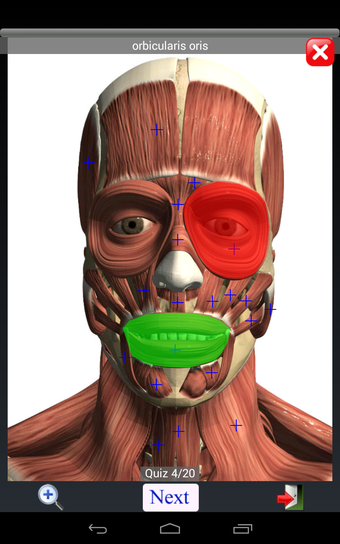

Anatomy Quiz Free es una aplicación de Android de Education Mobile que ofrece una amplia gama de cuestionarios para ayudar a los usuarios a aprender anatomía humana. La aplicación cuenta con más de 500 cuestionarios que ponen a prueba tu capacidad para identificar la ubicación correcta de un objeto dado su nombre. Los cuestionarios se generan a partir de modelos de anatomía 3D virtuales, lo que los hace más atractivos e interactivos. La aplicación es gratuita y no hay versiones premium ni compras dentro de la aplicación.

La aplicación es compatible con los idiomas inglés, francés, español y alemán, lo que la hace accesible para usuarios de diferentes partes del mundo. Las imágenes de alta resolución son nítidas y claras, y la función de zoom con pellizco te permite acercar y alejar las imágenes para una mejor vista. El cuestionario de posición viene con un temporizador, lo que lo hace más desafiante y emocionante. Además, la aplicación tiene una función de transferencia a la tarjeta SD, lo que facilita su transferencia a otros dispositivos.